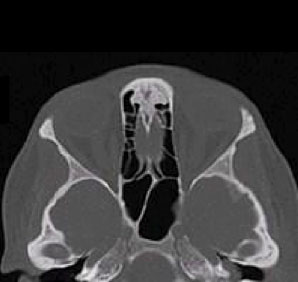

Tomografía computarizada Órbitas

< Volver a "Tomografía Computarizada (TC) con Inteligencia artificial"Está indicado para el estudio de los globos oculares o de los huesos de las órbitas (traumatismos).

Para el estudio del hueso en casos de traumatismos, no es necesaria ninguna preparación antes de la prueba.